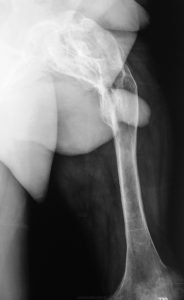

- Оссифицирующий;